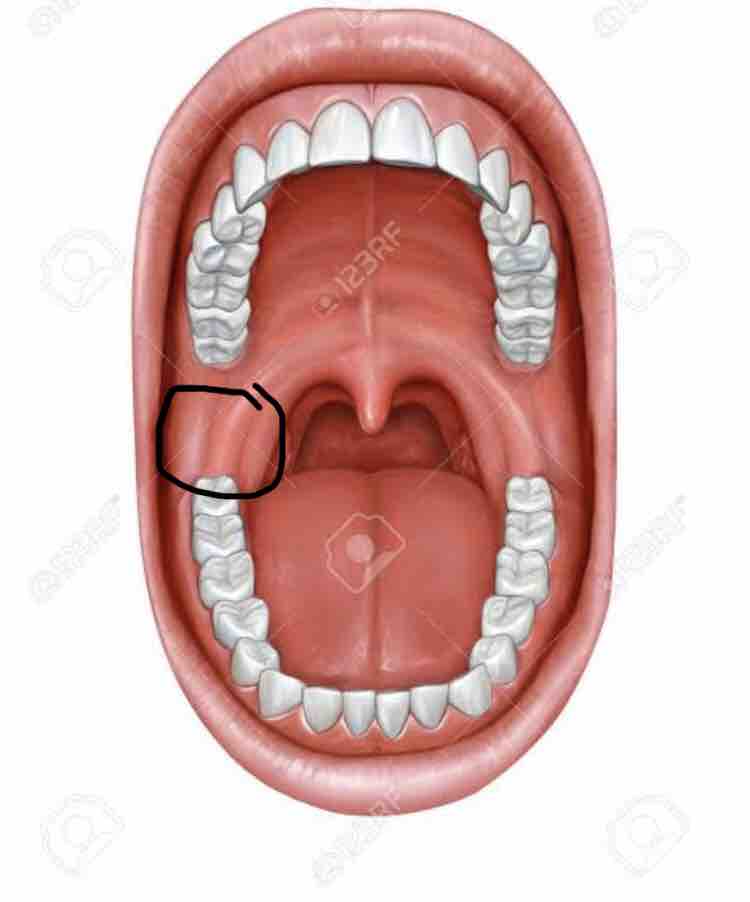

咽頭がんを早期発見するには そもそも咽頭とはどこのこと Helc